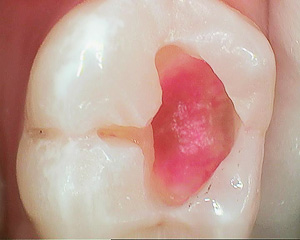

虫歯が染まる液体(う蝕検知液)を塗って虫歯を染め出します。

そして染まった部分だけを慎重に削り、虫歯以外の部分を絶対削らないようにしています。少しずつ削って行き、削ったら再びう蝕検知液で虫歯を染め出します。

この工程を何回も繰り返し、虫歯が染まらなくなるまで慎重に、かつ確実に虫歯を削り取ります。

こうして丁寧にすることによって、歯にダメージを与えず、かつ虫歯を取り残さないようにしています。